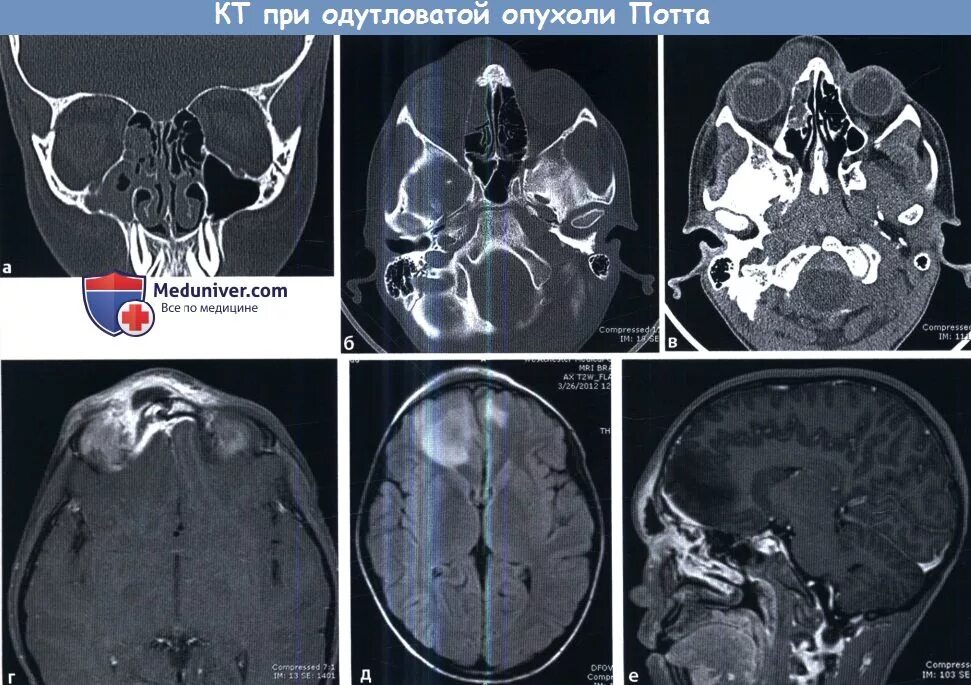

Синусит на кт